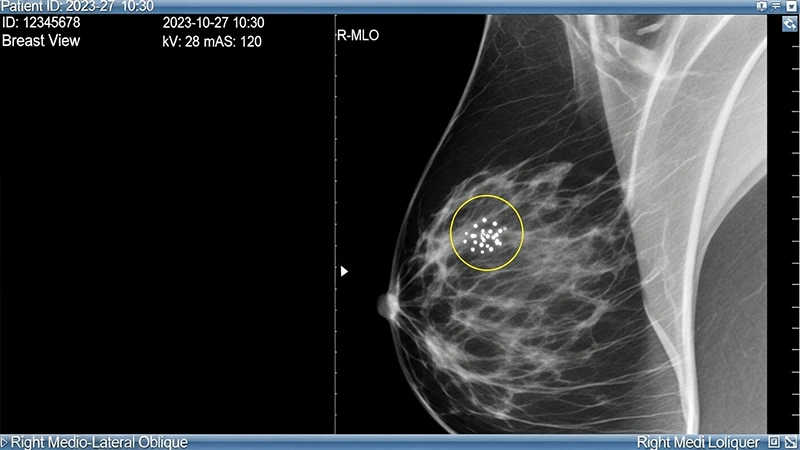

The primary challenge in reading screening studies is perceptual error. A small lung nodule or a tiny cluster of microcalcifications can be easily missed, especially when a radiologist is reading their 200th case of the day. This is where AI excels. An AI algorithm doesn't get tired or distracted. It can analyze every pixel of every image with the same level of scrutiny.

This is one of the earliest and most common applications of AI in imaging. A Computer-Aided Detection (or CADe) algorithm analyzes an image and places markers or circles on areas that it identifies as potentially abnormal. It acts as a "spell-checker" for the radiologist.

- In Mammography: CADe systems are trained to detect suspicious masses and clusters of microcalcifications, which can be an early sign of breast cancer.

The radiologist then reviews these marks. They use their expertise to decide if the AI's finding is a true abnormality or a "false positive" (e.g., normal overlapping blood vessels). The final diagnosis is always made by the human.